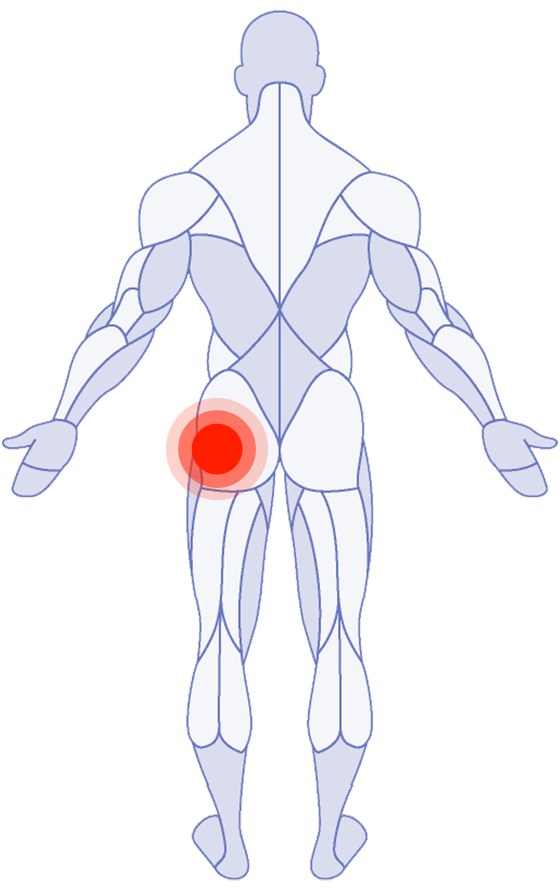

Where do you need attention?